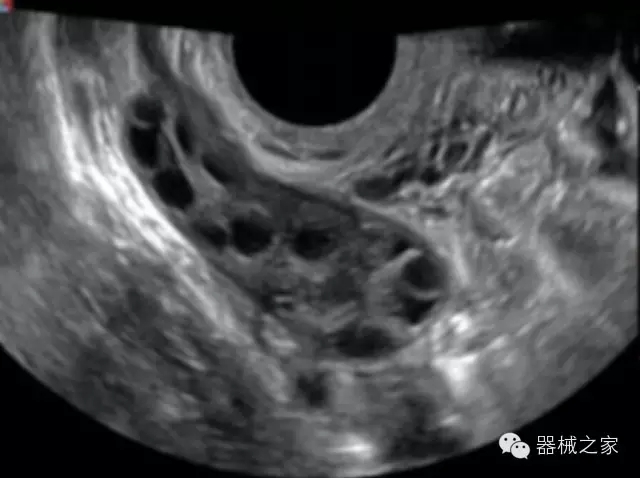

臨床圖片賞析

產(chǎn)品特點

優(yōu)異的成像技術

·亞陣元技術:獨有的亞陣元技術,對獨立晶片做二次切割,減少旁瓣偽像,增加臨床診斷的準確性;

·μ-Scan微米成像技術:開立獨有的μ-Scan技術,還原出真實細膩、層次對比優(yōu)異的二維圖像;

·倒相諧波成像技術:倒相諧波技術在去除基波信號的基礎上獲取兩倍二次諧波信號,提高組織圖像的對比分辨力;

·智能微血流成像技術:智能微血流捕捉技術可以提取出隱藏在背景噪聲中的弱血流信號,大大提高低速血流的敏感性;

全面的臨床解決方案

超聲科常規(guī)領域應用

·移植S40高端臺式彩超高端平臺技術,滿足超聲科腹部、淺表、婦產(chǎn)科、心血管、肌骨等應用,提供超聲科完美解決方案;

·實時的彈性成像技術:提高了小器管(乳腺,甲狀腺、淺表軟組織腫瘤等)疾病鑒別診斷;

·IMT血管內(nèi)中膜自動測量:為血管性疾病評估提供了有效的評估手段;

·心功能綜合指數(shù)(TEI指數(shù)):用于左、右心室整體心臟收縮舒張功能評估的測量方法;

·全方位可調(diào)M型:有利于更好的觀察心腔大小及室壁階段性運動的異常情況;

·組織多普勒成像(TDI):TDI可定量評價心肌運動,判斷是否有局部病變,還可評價早期的舒張功能;

·高效3D/4D成像技術:高速的4D幀頻,豐富的3D成像模式,智能斷層切片功能;

POC領域解決方案

·外觀小巧;

·穿刺增強技術:可有效提高進針區(qū)圖像分辨率,提高進針亮度,全面提高一次性穿刺的成功率;

全面的術中探頭解決方案

·小凸探頭:開放性手術,實時監(jiān)測病灶位置,提高手術成功率,可應用于麻醉科、肝膽外科、腫瘤外科、神經(jīng)外科、泌尿外科等手術;

·L型線陣探頭:高分辨率圖像,清晰顯示病灶位置,提高手術成功率,可應用于麻醉科、胸外科、肝膽外科、腫瘤外科、神經(jīng)外科、泌尿外科等應用;

·MPTEE:經(jīng)食道探頭術中監(jiān)測,可測量心臟前負荷(左室舒張末期大小、右房大?。⑿呐叛?、后負荷、收縮功能、室壁運動分析、肝靜脈血流(與中心靜脈壓相關)等,術后還能及時評估手術效果評估;

·獨有的大角度及實時溫控技術,能同一切面顯示宮頸及宮體,有效減低了患者的痛苦,及保護粘膜保證了醫(yī)療安全;

高效的人機工程學設計

·15‘’高清醫(yī)用顯示器;

·內(nèi)置雙探頭接口;

·可升降臺車,1拖3探頭擴展器;

·m-Tuning一鍵優(yōu)化;

CFDA注冊證編號

·粵食藥監(jiān)械(準)字20132230491